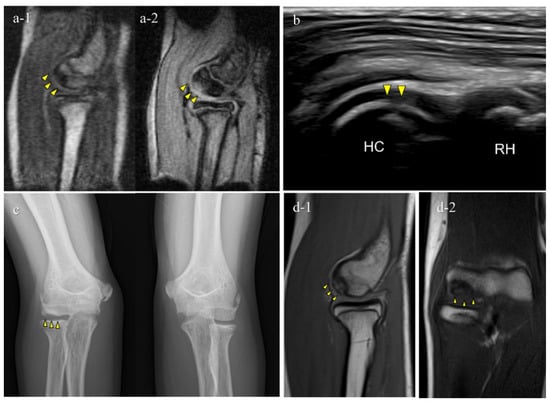

Figure 5. A false-negative OCD case with mobile MRI (Case 1): Mobile MRI (−), US (+). (a) Mobile MR (magnetic resonance) images: a-1, T1WI sagittal image; a-2, T2*WI sagittal image: Mobile MRI with poor imaging quality with low signal/noise ratio. Although the signal change was barely visible from the anterior to the humeral capitellum, we could not detect it; (b) US image of the posterior longitudinal view: US imaging revealed obvious subchondral bone irregularity; (c) X-p AP view with elbow 45° flexed: X-p 45° showing the lesion with fragmentation in the central capitellum, stage II OCD; (d) 3T MR images: d-1, proton density-weighted images (PDWI) sagittal image; d-2, PDWI- fat-suppressed (FS) sagittal image: 3T MRI easily detected the lesion. HC, humeral capitellum; RH, radial head; yellow arrowheads, lesions.